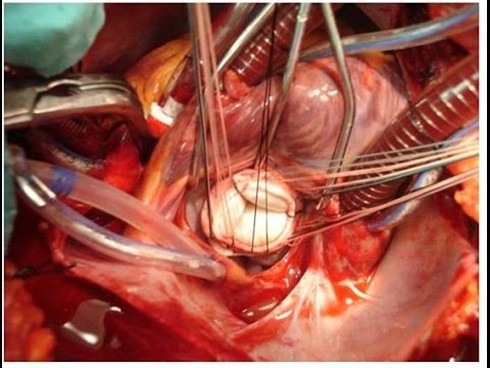

Một ca phẫu thuật tim (ảnh minh họa) |

Kết quả siêu âm tim cho thấy, khối u nhầy nhỉ phải lớn 42x69mm, che lấp van ba lá. Máu từ nhĩ phải xuống thất phải bị hạn chế bởi khối u, gây tình trạng ứ máu ở hệ tĩnh mạch, dẫn đến phù và suy tim. U tim là một bệnh lý rất nguy hiểm, hiếm gặp, có thể đe dọa đến tính mạng bệnh nhân. Các khối u tim thường được phẫu thuật để cắt bỏ. Cụ Xuân có sức khỏe yếu, nhưng ngày 1-12, các bác sĩ Đơn vị tim mạch - Bệnh viện Hoàn Mỹ Đà Nẵng đã cắt bỏ thành công khối u tim của bệnh nhân.